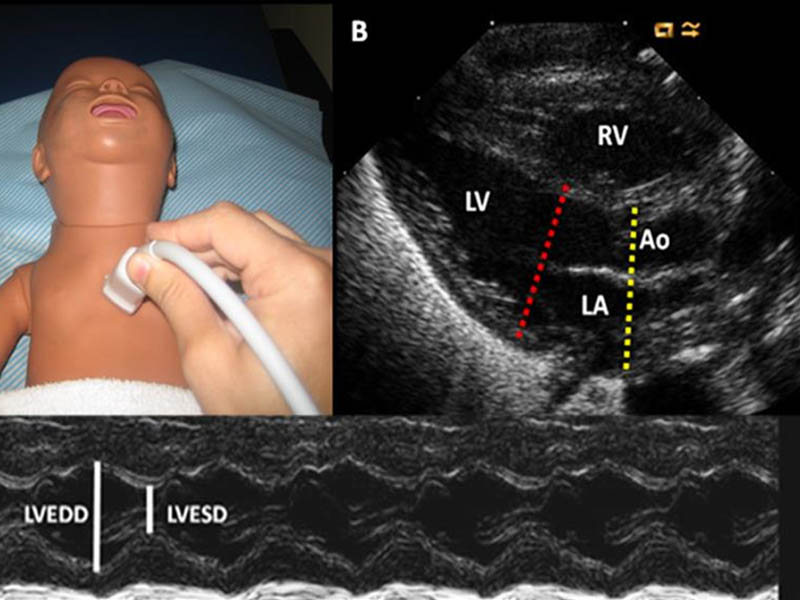

Echocardiography Neonatal